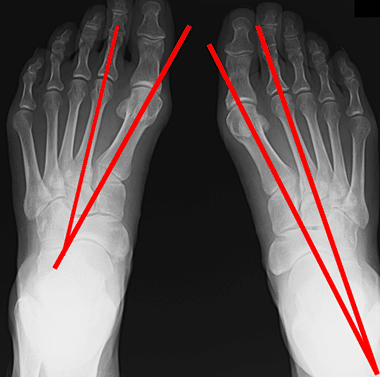

外反母趾のレントゲン写真

外反母趾の方のレントゲンでは、このように写ります。

そして、レントゲン上で、どのくらい曲がっているかを線を引いて角度を出します。

その角度が基準より大きければ、外反母趾という診断が付き、治療が開始されます。